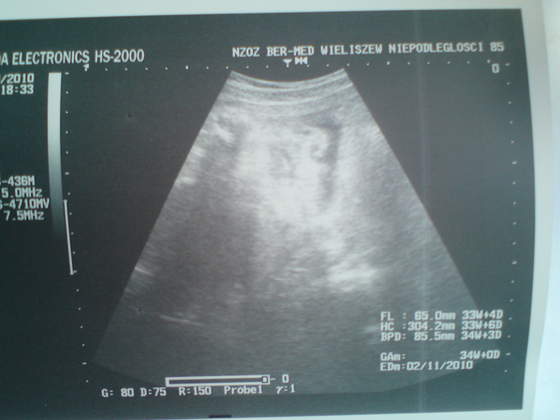

Gratuluję wszystkim udanych wizyt. Ja też dziś byłam na usg

Sebastianek jest zdrowiutki i ku naszemu zdziwieniu jest spory tak mi się przynajmniej wydaje , waży 2164 g. Moje wszystkie badania wyszły super i w ogóle się świetnie czuję .... Teraz trzeba tylko oczekiwać. Mój gin powiedział , że będę miała w 99% cc bo dzidziuś się nie przeciśnie przez taką chudzinkę jak ja..... On ma mi napisać skierowanie na cc ale i tak ostatecznie decyduje lekarz prowadzący w szpitalu. Ale podobno przy tak wąskiej miednicy nie powinni nawet mnie cisnąć na poród naturalny. Nie będę ukrywać że daje mi to pewien komfort psychiczny.... wiem że wiele z was uważa poród naturalny za najlepszy sposób przyjścia na świat ale ja uważam , że cc nie jest takie złe jak je malują!

Wrzucam swoje aktualne foto i zdjęcie mojej kochanej mordeczki jak się dobrze przypatrzycie to widać dobrze nosek i usteczka, zupełnie tak jakby był w kapturze